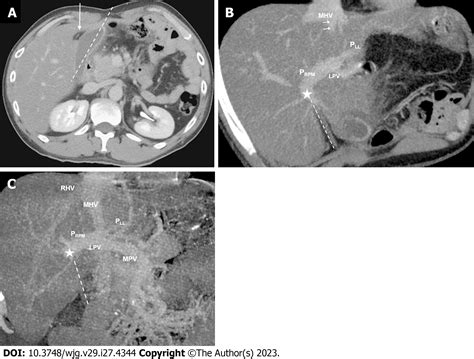

Computed Tomography (CT) Scan

CT scans provide detailed cross-sectional images of the body, allowing for a more comprehensive evaluation of the ligamentum teres hepatis and surrounding structures. CT scans can detect:

• Anatomical Abnormalities: Structural abnormalities of the ligamentum teres hepatis can be visualized.

• Tumors: Detailed images of tumors within or near the ligamentum teres hepatis can be obtained.

• Inflammation: Inflammatory changes in the ligamentum teres hepatis can be detected.

Magnetic Resonance Imaging (MRI)

MRI uses magnetic fields and radio waves to create detailed images of internal structures. It is particularly useful for evaluating soft tissues and can provide valuable information about the ligamentum teres hepatis. MRI can detect: